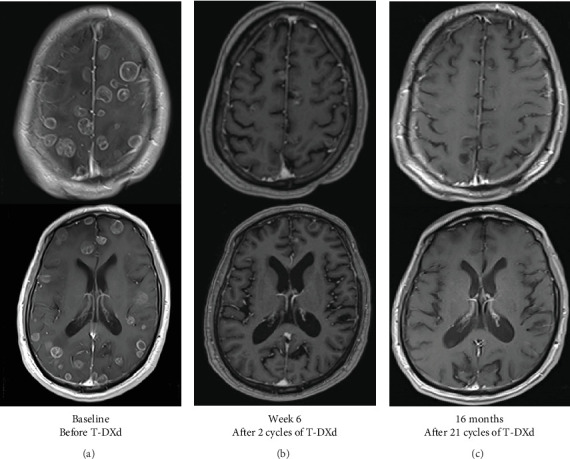

In non-small-cell lung cancer (NSCLC), activating human epidermal growth factor receptor 2 (HER2) mutations are found in a small subset of patients and are associated with a higher incidence of brain metastases (BMETSs), conferring poor survival outcomes. Trastuzumab deruxtecan (T-DXd) was recently approved as a second-line agent for use in patients with previously treated, unresectable, or metastatic HER2-mutated NSCLC. We present a case of HER2-mutated NSCLC with BMETS, treated with T-DXd to defer whole-brain radiotherapy (WBRT) because of the concern of long-term neurotoxicity. He initially also received bevacizumab to address the cerebral edema, which allowed stopping corticosteroids. After the first two doses, the patient had remarkable clinical and imaging (brain and systemic) responses without progression after more than 1 year of treatment. T-DXd may be an effective and durable therapy for patients with HER2-mutated NSCLC with brain metastases in situations where intracranial disease would otherwise warrant WBRT. Clinical trials are needed to understand the efficacy and durability of T-DXd in NSCLC with BMETS and the optimal sequence of available therapies.